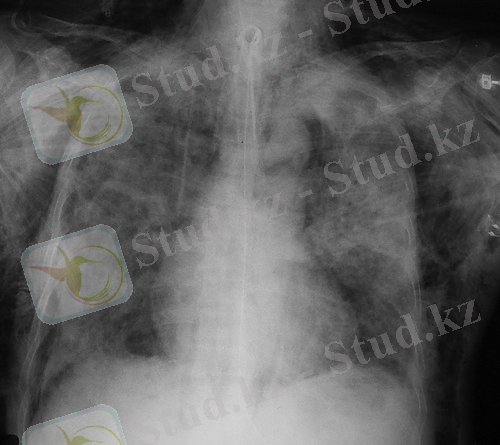

Пневмоторакстың рентгенологиялық белгілері-

- Тері астылық эмфизема- қорытынды рентгенограммада «қабатталған қамыр» түрінде көрінеді (сурет 6), толық тері асты эмфиземасында қабырғалар құрылымы, өкпе тіні нашар жіктеледі, үлкен кеуде бұлшықеті бойымен радиальді «сәулелер» анықталады (сурет 7) .

- өкпеліе суреттің жоғалуымен «ағару» аймақтары (сурет 8)

- өкпе шеті анықталады (сурет 8) .

Сурет 8. Пневмоторакс кезінде қорытынды рентгенограмма:

Сызықтармен өкпе суреті және өкпе шеті жойылған «ағарған» бөліктері көрсетілген.